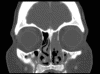

Image of the Case: CT scan, coronal view, of the sinuses reveals an opacified left ostiomeatal unit on the left and thickening of the mucosa on the right (Panel A). CT scan, axial view. The hard palate and maxilla show destructive changes and fractures causing a “moth-eaten” appearance (Panel B).